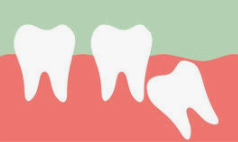

사람의 턱은 크기가 한정되어 있기 때문에 수용할 수 있는 치아의 갯수가 한정적입니다. 턱이 발달되고 큰 사람들은 사랑니가 자라나도 정상적으로 자라나 문제가 없을수도 있지만 사랑니가 자라는 대부분의 사람들은 수용할 수 있는 치아의 갯수가 초과되기 때문에 치아가 자라날 자리가 없어 잇몸을 비집고 자라거나 잇몸안에서 나오지 못하는 경우가 대부분 입니다.

그렇기 때문에 어금니 신경을 건들여 통증이 있고 좁은 잇몸을 비좁고 나오려고 하기 때문에 붓는 증상이 나타나게 됩니다.